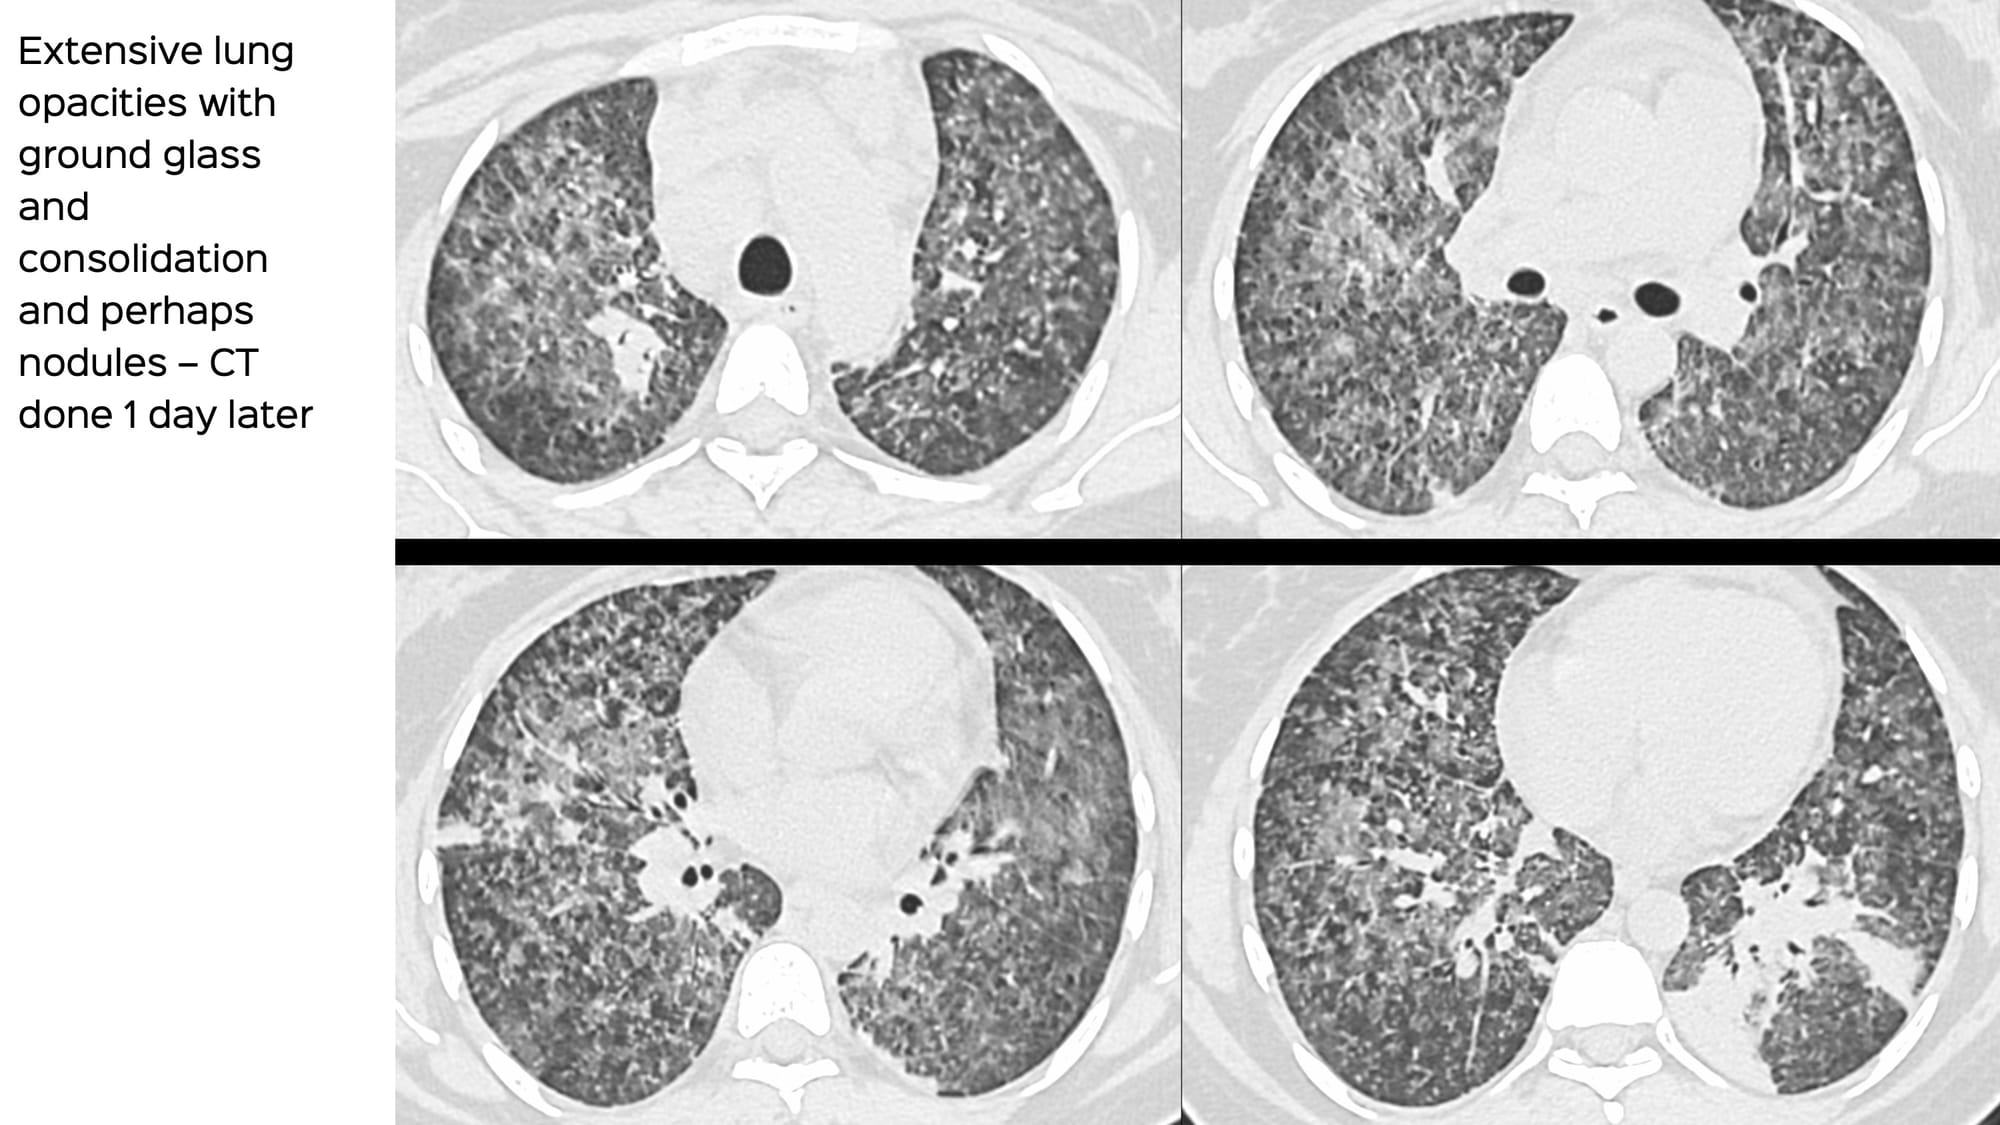

The CT done 1 day later showed diffuse ground glass and focal consolidation.

The least involved areas (the apices) showed classic miliary nodules.